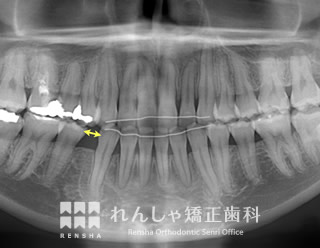

過蓋咬合(14歳 治療期間:2年8か月)

正中離開(前歯の間にあいた隙間)が気になり来院されましたが、過蓋咬合(深い噛み合わせ)が主な原因になっていることがあきらかでした。

下歯列形態は左右非対称になり、右奥歯の噛み合わせがすれ違っています(鋏状咬合)。この噛み合わせを放置すると、上前歯の前突やすきっ歯はさらに悪化し、右奥歯は全く噛めなくなってしまいます。

まず過蓋咬合と右奥歯の噛み合わせを改善し、その後上前歯を後退させました。

| 主訴 | 前歯の隙間と歯ぎしり |

|---|---|

| 診断名 | Angle Class II 過蓋咬合を伴う上顎前突 |

| 初診時年齢 | 14歳5か月 |

| 装置名 | マルチブラケット装置 |

| 抜歯非抜歯 | 上顎両側第一小臼歯(合計2本) |

| 治療期間 | 2年8か月 |

| 費用の目安 | 約89万円+消費税(検査料金、都度の処置費用等も合わせた総額) |

| リスク副作用 | 歯の移動に伴う軽微な歯根吸収、歯槽骨吸収、歯肉退縮(いずれも本症例ではほぼ無し)、矯正器具装着中のカリエスリスク増大(本症例ではカリエス発生無し) |